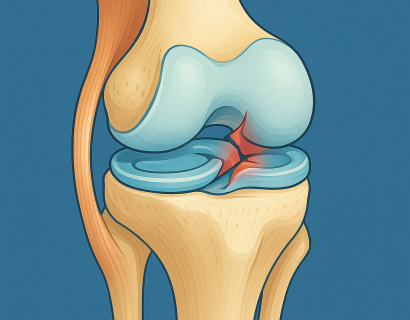

Мениски — это полулунные хрящевые прокладки, и, несмотря на их эластичность и прочность, они довольно часто повреждаются.

Коленный сустав — один из самых сложных и уязвимых суставов в человеческом теле. Он несёт огромную нагрузку каждый день, особенно у активных людей и спортсменов.